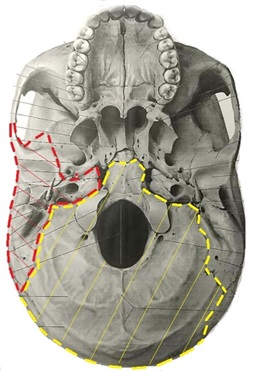

頭蓋骨ついて(側頭骨と後頭骨の関係性)

頭蓋骨を横から後ろの断面から見てみよ

う。黄色の点線がいわゆる

後頭骨(こうとうこつ)とよばれるものを

緩めて頭蓋骨を調整します.

赤い点線側頭骨(そくとうこつ)であり

これらはパズルのように連動しています

側頭骨のバランスが崩れると解剖図を見

ても分かると思いますが顎の位置(関

節円盤)が近くにある為、顎の噛み合

わせなども当然、変化していきます。

かみ合わせが悪くなると顎の違和感から

始まり左右の顎の「ズレ」という感覚

にもなります。下から見た物です。

下顎は下の方に掲載

されていて位置も説明があります